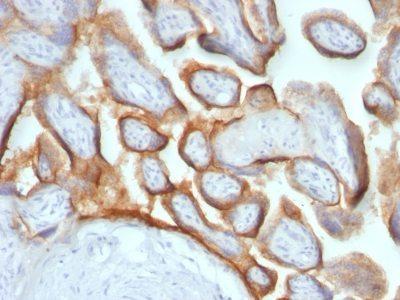

This MAb reacts with a protein of 22 kDa, identified as β sub-unit of HCG. It does not cross react with the α sub-unit. HCG is a glycoprotein, which is secreted in large quantities by normal trophoblasts. It is present only in trace amounts in non-pregnant urine and sera but rises sharply during pregnancy. HCG is composed of two non-identical, non-covalently linked polypeptide chains designated as the alpha and beta subunits. The alpha subunit is identical to that of thyroid stimulating hormone (TSH), follicle stimulating hormone (FSH), and luteinizing hormone (LH). hCG MAb detects cells and tumors of trophoblastic origin such as choriocarcinoma. Large cell carcinoma and adenocarcinoma of the lung demonstrate anti-hCG positivity in 90% and 60% of cases respectively. 20% of lung squamous cell carcinomas are positive. hCG expression by non-trophoblastic tumors may indicate aggressive behavior.Primary antibodies are available purified, or with a selection of fluorescent CF® Dyes and other labels. CF® Dyes offer exceptional brightness and photostability. Note: Conjugates of blue fluorescent dyes like CF®405S and CF®405M are not recommended for detecting low abundance targets, because blue dyes have lower fluorescence and can give higher non-specific background than other dye colors.

Positive Control

Placenta

IHC, FFPE (verified)

IHC (FFPE) (verified)

Higher concentration may be required for direct detection using primary antibody conjugates than for indirect detection with secondary antibody|Immunohistology formalin-fixed 0.5-1 ug/mL|Staining of formalin-fixed tissues requires boiling tissue sections in 10 mM citrate buffer, pH 6.0, for 10-20 min followed by cooling at RT for 20 minutes|Optimal dilution for a specific application should be determined by user